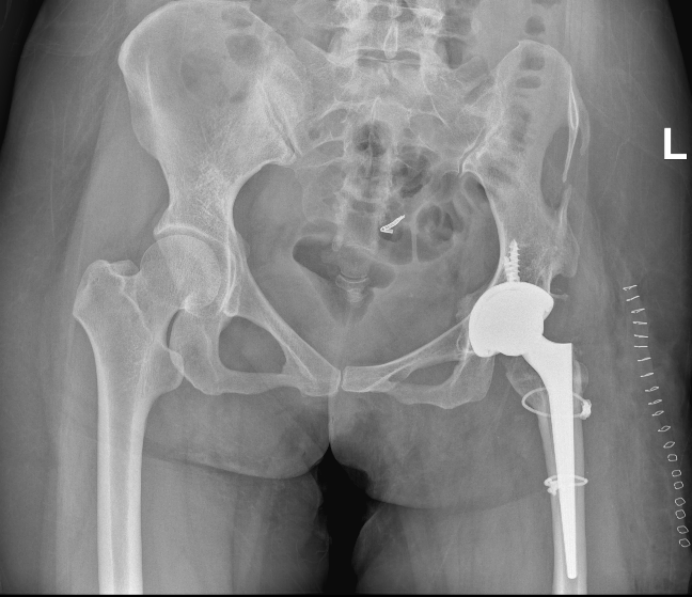

当河北医大一院

髋关节中心主任刘长城

看到她的 X 光片

呈现的是

几乎「消失」的髋关节结构

原有的股骨头已不复存在

髋臼被增生骨质封闭

股骨上段严重变形

这不是常规的关节置换

更像是在失去

原有解剖标志的区域内

重新寻找一个

可以让假体安放的位置

手术采用前路 DAA 技术展开

当切口打开后

真正的挑战才完全显现

患者髋臼发育特别小

髋臼的位置

被股骨头填满

长在一起

医生必须在

有限的操作空间内

精确找到真正髋臼的位置

并在合适的位置

打造一个仅能

容纳最小号髋臼假体的窝

患者股骨髓腔异常纤细

无法容纳最小号的假体

刘主任通过微创的切口

在有限的操作空间里

对狭窄的髓腔进行精细处理

最终把最小号的股骨柄放入其中